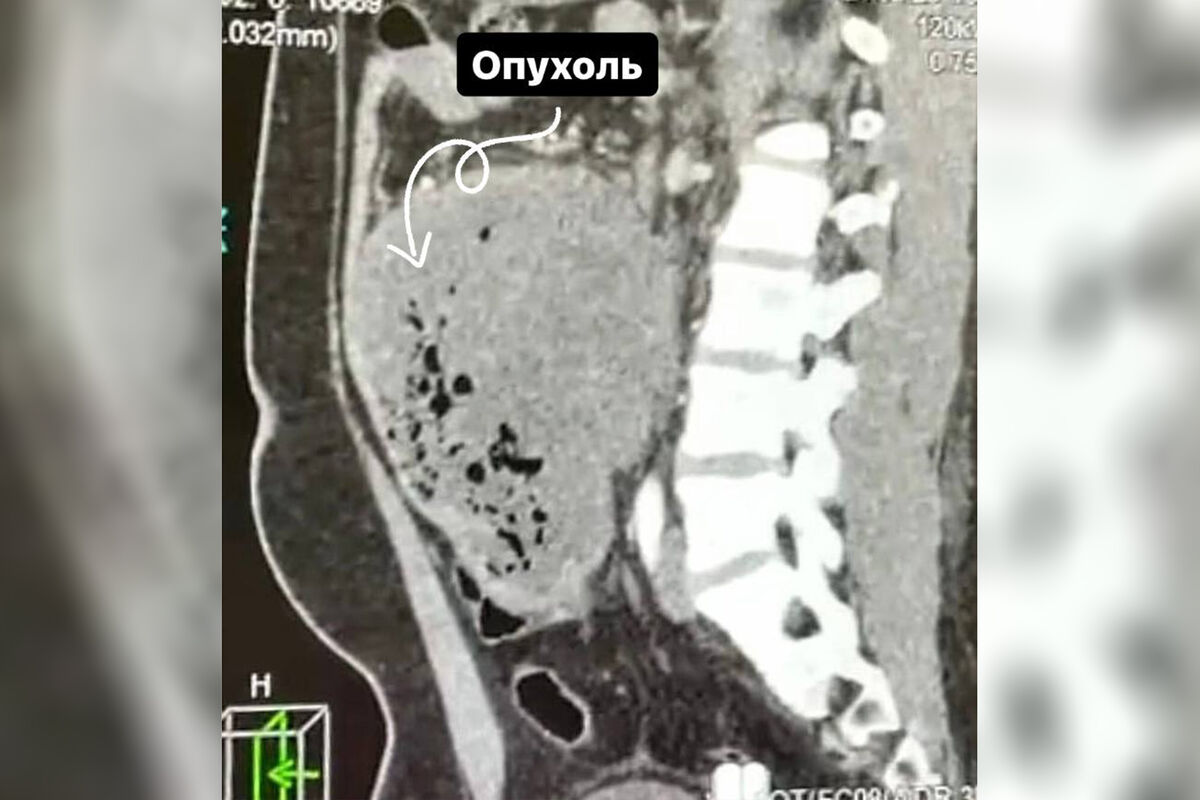

Врачи Долгопрудненской больницы прооперировали 21-летнего пациента со злокачественной опухолью размером 15 см, новообразование мужчина принял за кишечную инфекцию. Об этом сообщает минздрав Московской области.

В ходе обследования в брюшной полости пациента медики обнаружили новообразование. Выяснилось, что неприятные симптомы беспокоили молодого человека в течение месяца, он обращался в частную клинику, но тогда диагностика не выявила никаких отклонений.

«Ситуацию осложняла локализация опухоли, она находилась в труднодоступном для удаления месте — между аортой и нижней полой веной. Под общим наркозом мы удалили 15-сантиметровое образование вместе с участком кишки», — рассказал заведующий хирургическим отделением больницы Сергей Лисин.

Хирургическое вмешательство длилось пять часов, опухоль удалось удалить. Гистологическое исследование показало, что новообразование было злокачественным. Пациент уже выписан на амбулаторное лечение и будет наблюдаться у онколога по месту жительства.